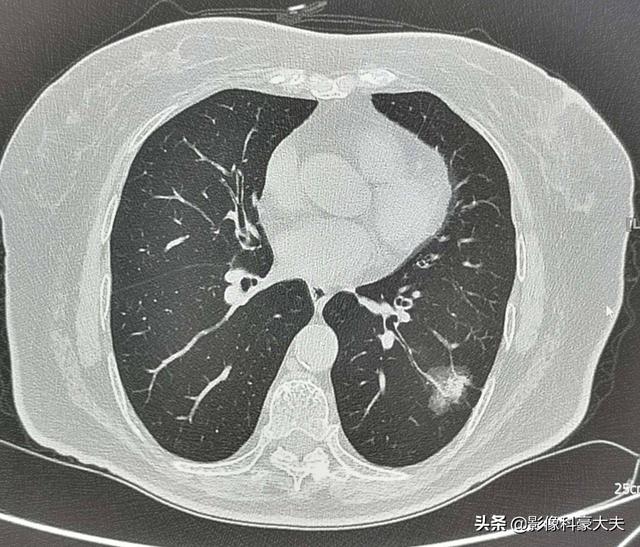

2. nodules pulmonaires sous-solides de plus de 8 mm de diamètre (nodules mixtes de verre et de terre).

Par exemple, cette femme d'âge moyen présentant un nodule de verre à membrane mixte de 2,2 cm dans le poumon inférieur gauche est un nodule à haut risque, qui présente en fait les signes classiques d'un adénocarcinome pulmonaire, à savoirOmbre en verre dépoli bien définie avec entrée et épaississement vasculaire, signe d'insufflation bronchique, atteinte pleurale distale, pathologie chirurgicale de l'adénocarcinome pulmonaire invasif.Ce type de lésion n'est pas recommandé pour le suivi et doit faire l'objet d'un examen plus approfondi afin d'éviter les métastases et les retards de traitement.

Cependant, nous devons également reconnaître que tous les nodules à haut risque ne sont pas des cancers du poumon, et que les nodules plus petits que les critères de haut risque énumérés ci-dessus peuvent également être des cancers du poumon ! Les lignes directrices ne font que tourner autour du pot.